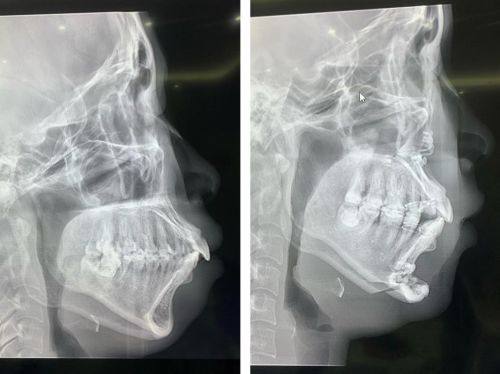

1. 凸嘴矫正:凸嘴不仅影响面部美观,还可能影响口腔功能。尹泰镐院长在凸嘴矫正方面有着丰富的经验。他会根据患者的具体情况,制定个性化的矫正方案。对于一些轻度凸嘴患者,可能采用牙齿矫正的方式,通过调整牙齿的排列来改善凸嘴情况;而对于较为重度的凸嘴患者,则可能结合外科手术进行矫正。他的矫正技术能够有效改善面部轮廓,让患者拥有更加美观的面容。

2. 地包天矫正:地包天会导致面部不协调,影响患者的自信心。尹泰镐院长能够正确判断地包天的成因和类型,采用合适的矫正方法。对于牙性地包天,他可以通过牙齿矫正来调整牙齿的咬合关系;对于骨性地包天,则可能需要进行手术治疗。他的矫正方案能够较大程度地修复患者正常的咬合功能和面部形态。